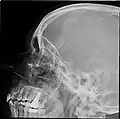

Lateral projection of the paranasal sinuses